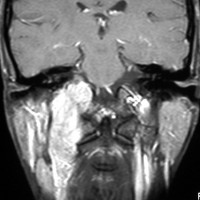

左は1991年,右は2006年のMRI画像です。15年間で腫瘍のサイズは変わっていません。

1991年に50代の女性にみつかったものでした。黄色に示したルートで摘出できないわけではありませんが,右後頭部が腫れてきたという訴えとホルネル症候,軟口蓋麻痺しかなかったので,何も治療しないでほっておきました。2016年まで25年間観察し続けました。症状の悪化は全くなく元気に暮らしておられます。グロームス腫瘍はある一定の年齢になると増大しないという性質を持っている良性腫瘍です。これを大々的な頭蓋底外科手術で摘出するするという愚を犯してはなりません。